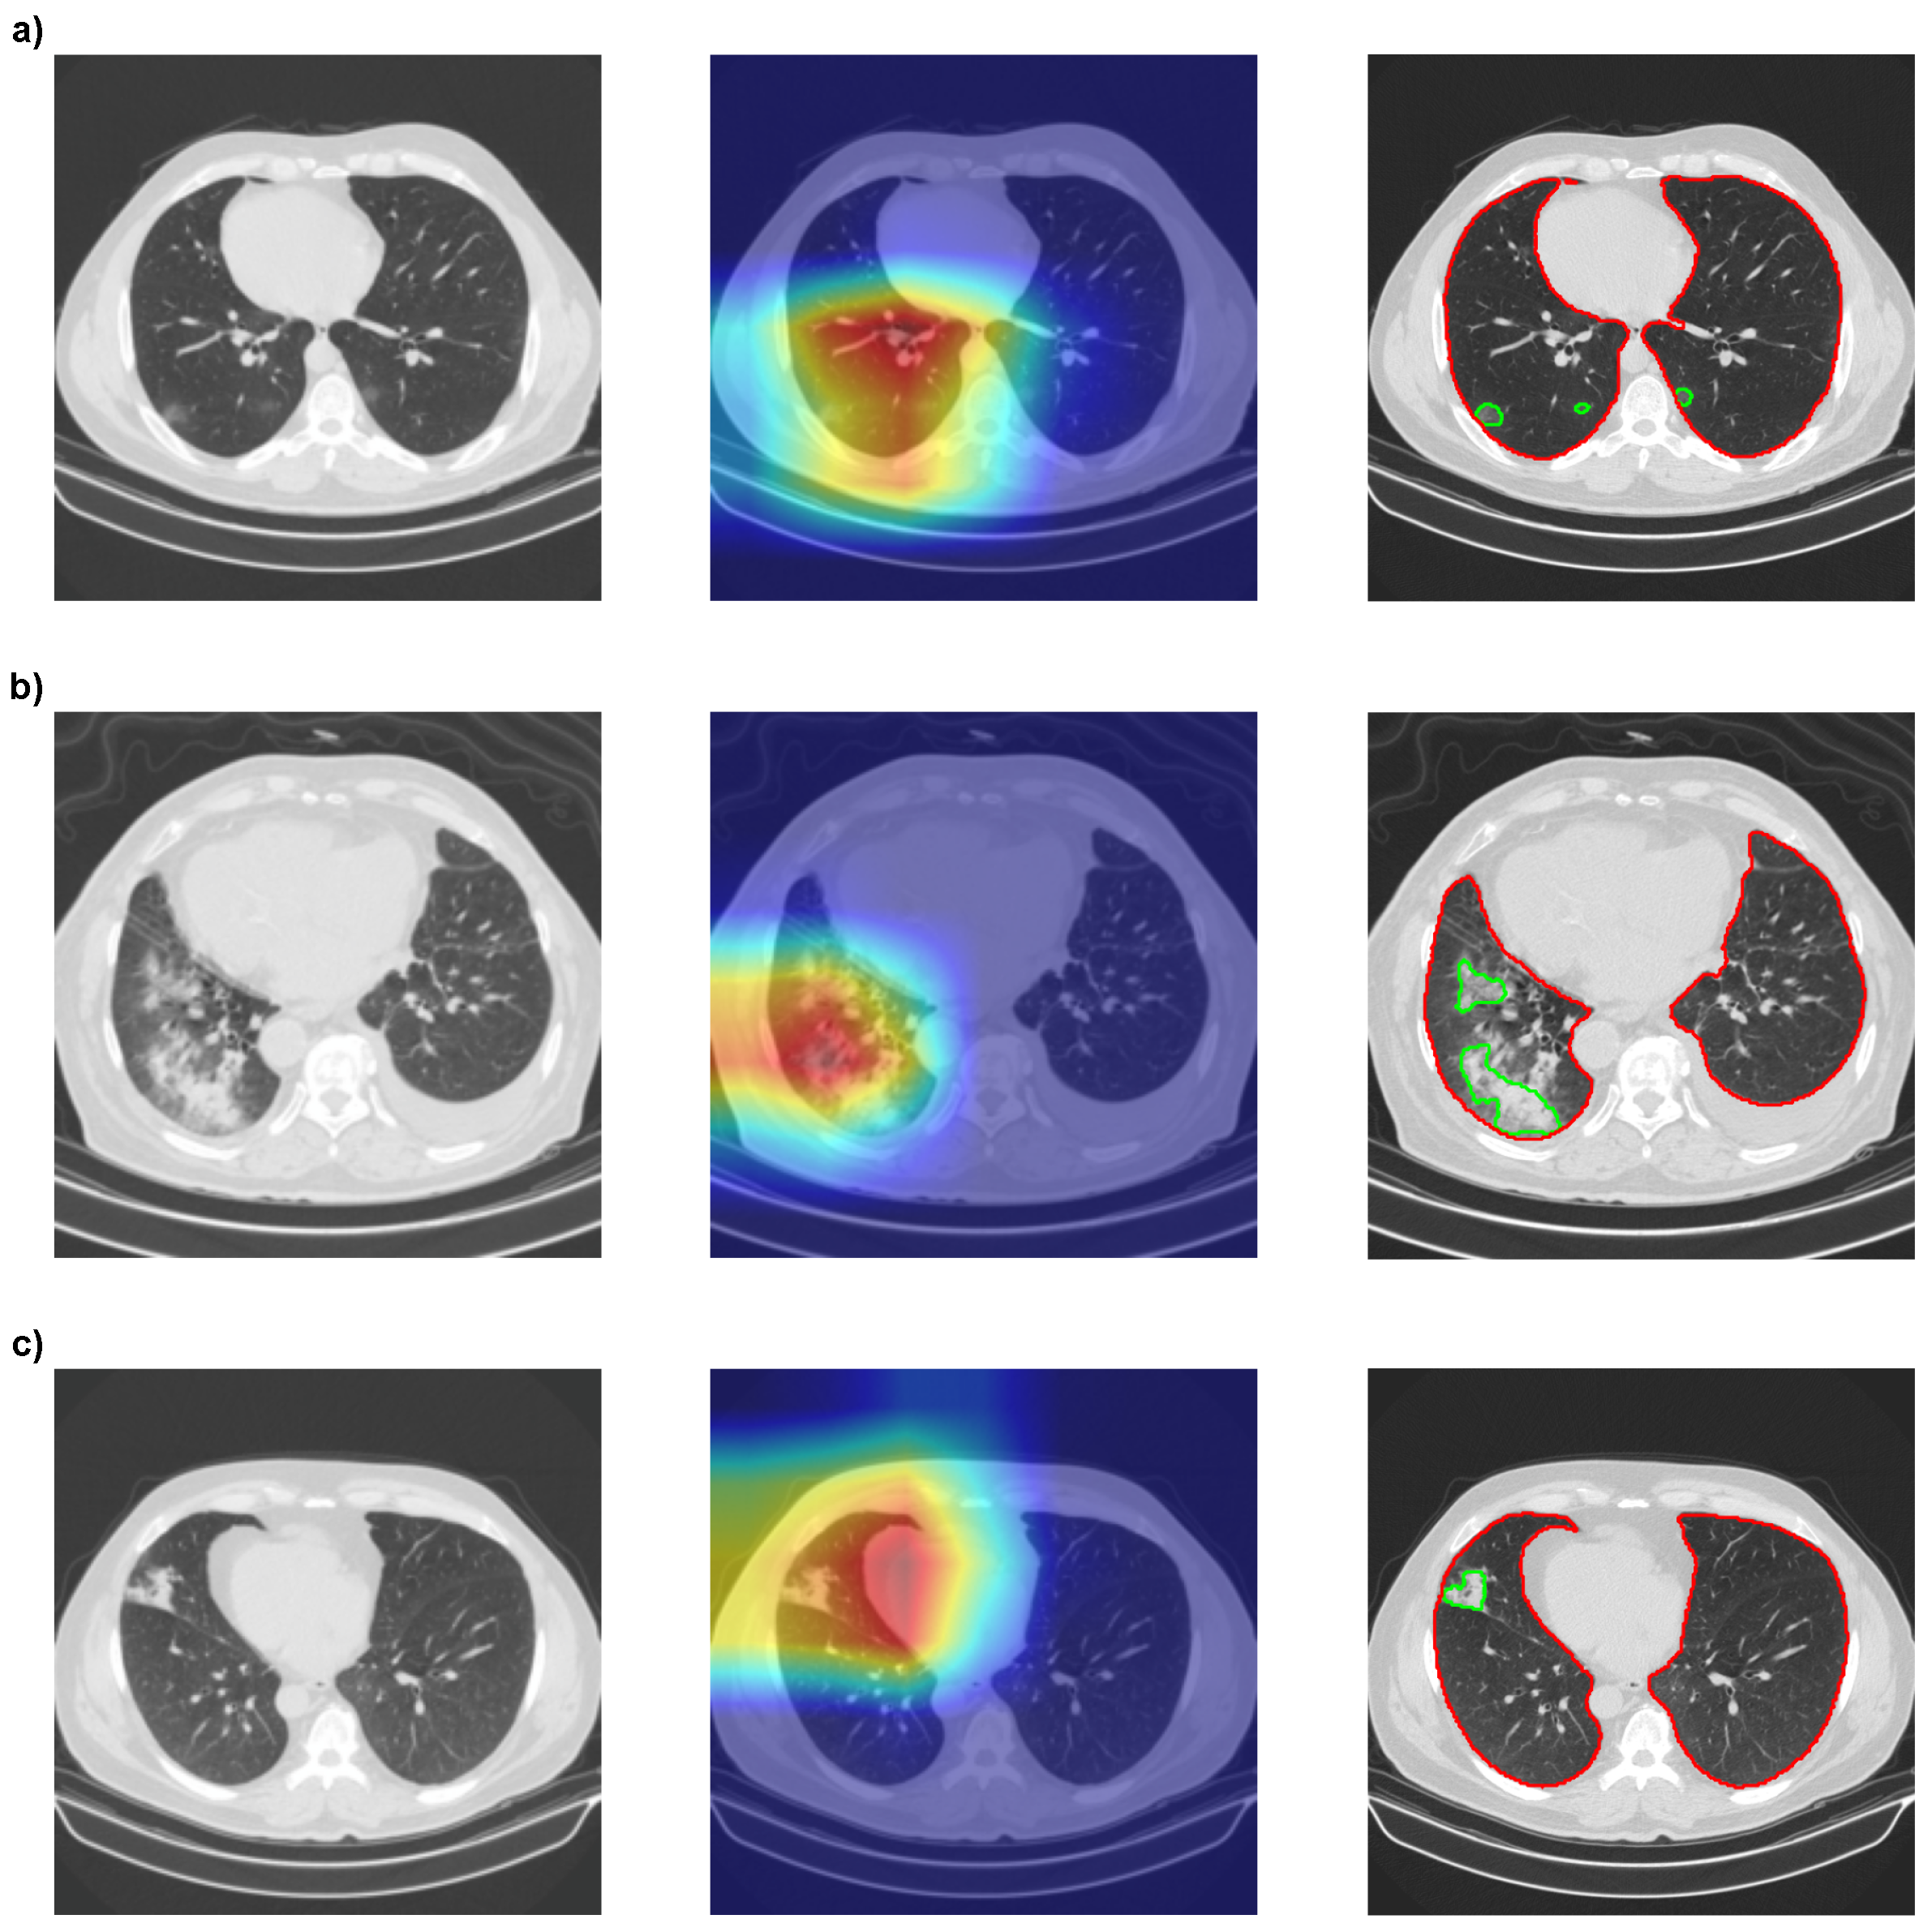

Then, we used GradCAMPlusPlus [56] to analyze the interpretability of our models with Densenet201. In Figure 9, we can see that the red spots, which highlight the most critical areas of the image for classification, mainly coincide with our segmentation results obtained with MobilenetV2 Unet.

The segmentation of COVID-19 or CAP lesions provides more information than the results of GradCAMPlusPlus, as it is possible to calculate the lesion area for each slice or full CT scan lesion volume. Furthermore, the GradCAMPlusPlus heatmap in Figure 9a might suggest that lesions only occurred in the left lung, while the segmentation showed lesions in both lungs. However, neither of the two methods could determine which specifications of the lesion were used by the CNNs to classify an image as COVID-19 or CAP. Thus, further interpretability is necessary, and RQ3 is answered.

Figure 9. Comparison between the interpretability of the XAI method with Densenet201 and the segmentation method with MobilenetV2 Unet. (a) Correctly classified COVID-19-positive slice. (b) Correctly classified CAP-positive slice. (c) CAP-positive slice wrongfully classified as COVID-19. XAI is presented as heatmaps, with red representing the most important region of the image for classification and green the least important.